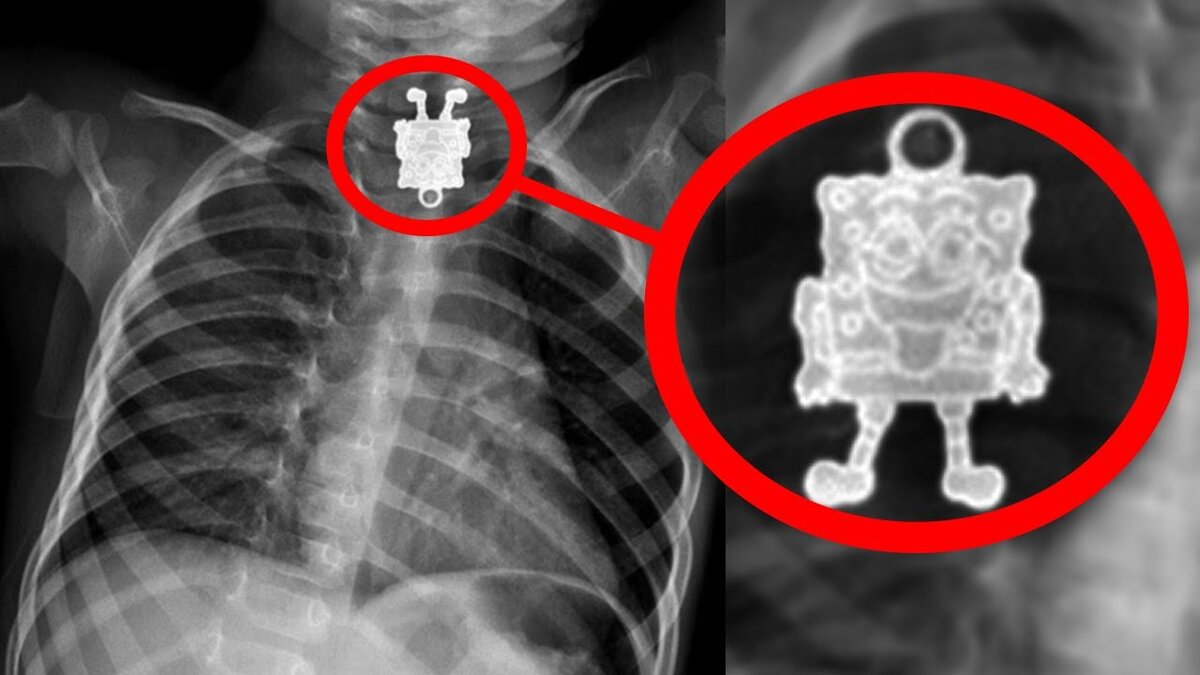

5) Губка Боб

Все любят губку боба квадратные штаны, и взрослые и дети. Неудивительно, что во многих домах на полу разбросаны фигурки персонажей мультика. Мы уверены, что Боб живет на дне тихого океана как и все его друзья, но иногда судьба может забросить бедолагу и в менее очевидные места. Одному из докторов довелось увидеть нечто на рентгеновском снимке своего пациента. Родители привели 16-месячного малыша к врачу, боясь, что он мог съесть что-то, что не нужно было есть. На снимке все выглядит как в фотошопе, очень уж четко видно фигурку. Она прям смотрит в упор на врача, которому придется ее вынимать. Это была часть ожерелья, которую малыш смог оторвать.